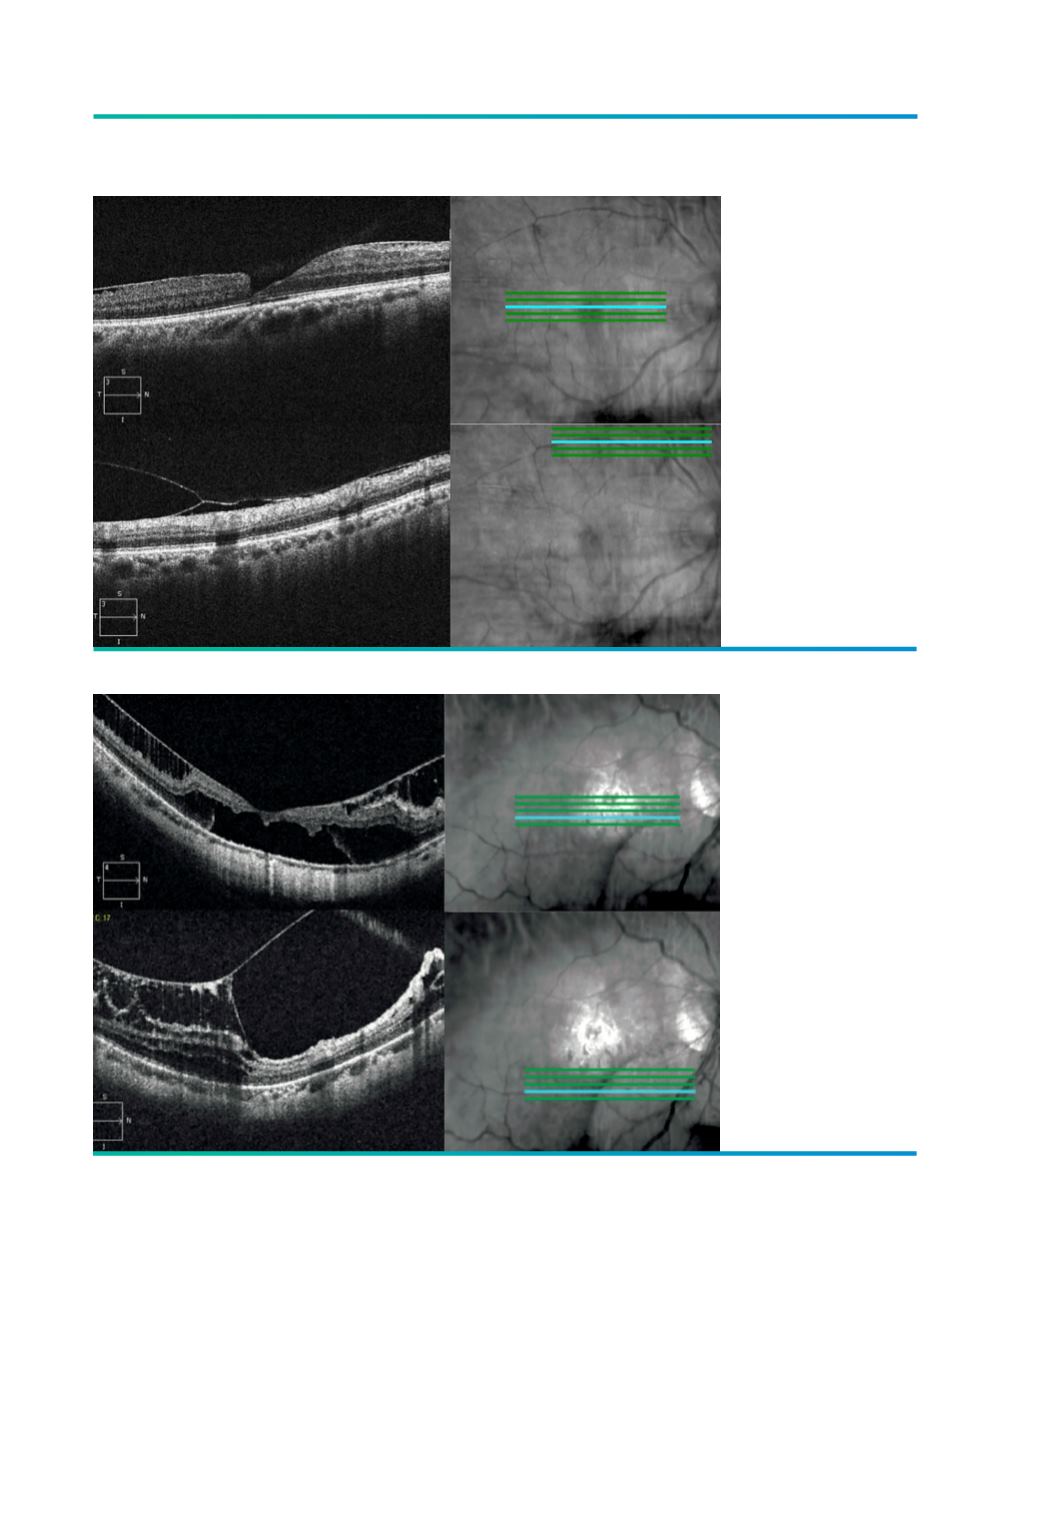

Figura 6.

Tracção vítreo-

retiniana – área foveal

e arcada temporal

superior.

Figura 7.

retiniana em

retinosquisis – área

foveal e área inferior à

fóvea.